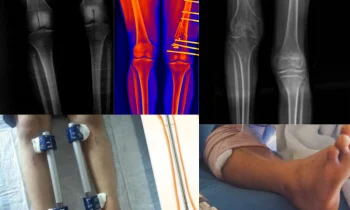

BACAK UZATMA AMELİYATININ MALİYETİ NE KADARDIR?

Leg Lengthening Surgery Cost Etkileyen Faktörler Hormona, genetik, çevresel ve diğer birçok faktöre bağlı olarak kısa boylu olanlar, boy uzatma ameliyatları ile bacak boylarını gözle görülür bir şekilde uzatabilirler. Cerrahi bir işlem olan bacak boyu uzatma ameliyatlarındaki maliyet ameliyatın yapıldığı klinikten...